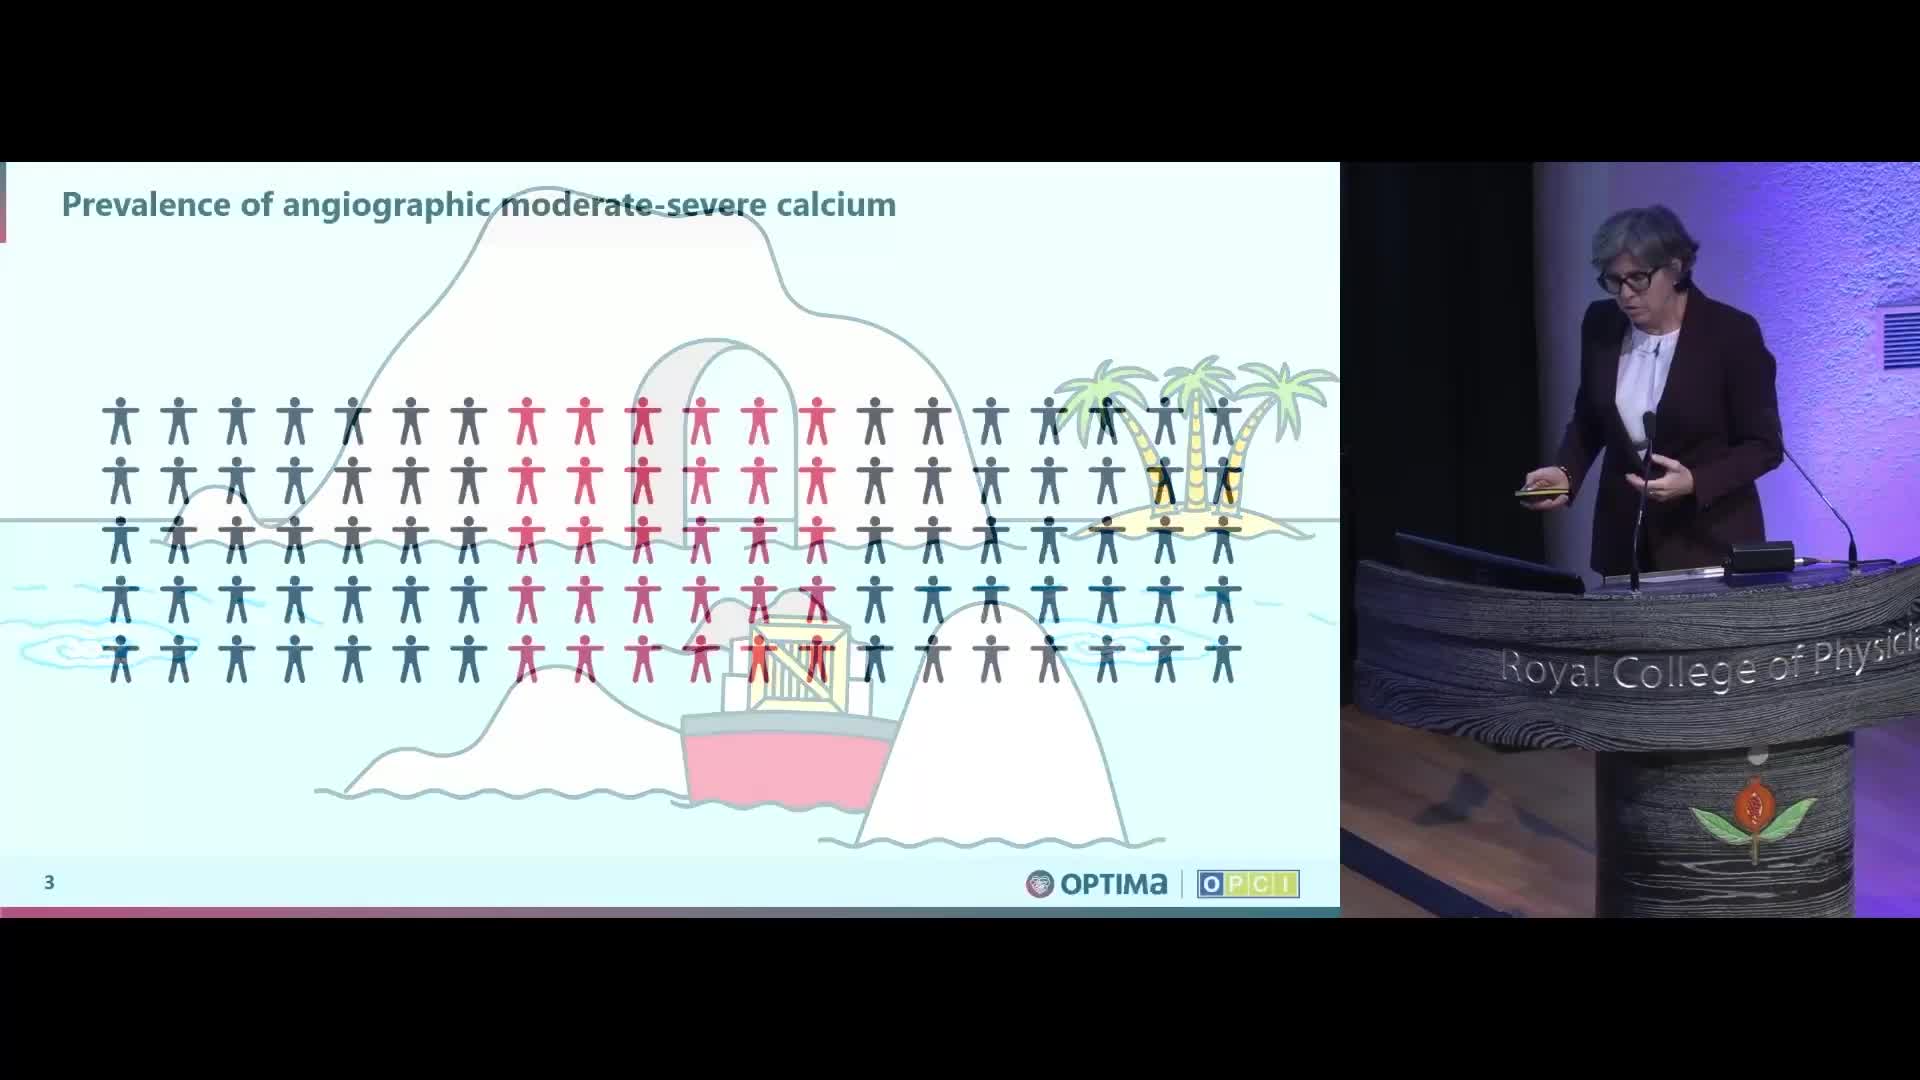

Session 2: Coronary calcium – too hard to crack?

Treatment of coronary arterial calcium (CAC) has being redefined. We explore the interaction between CAC and patient...